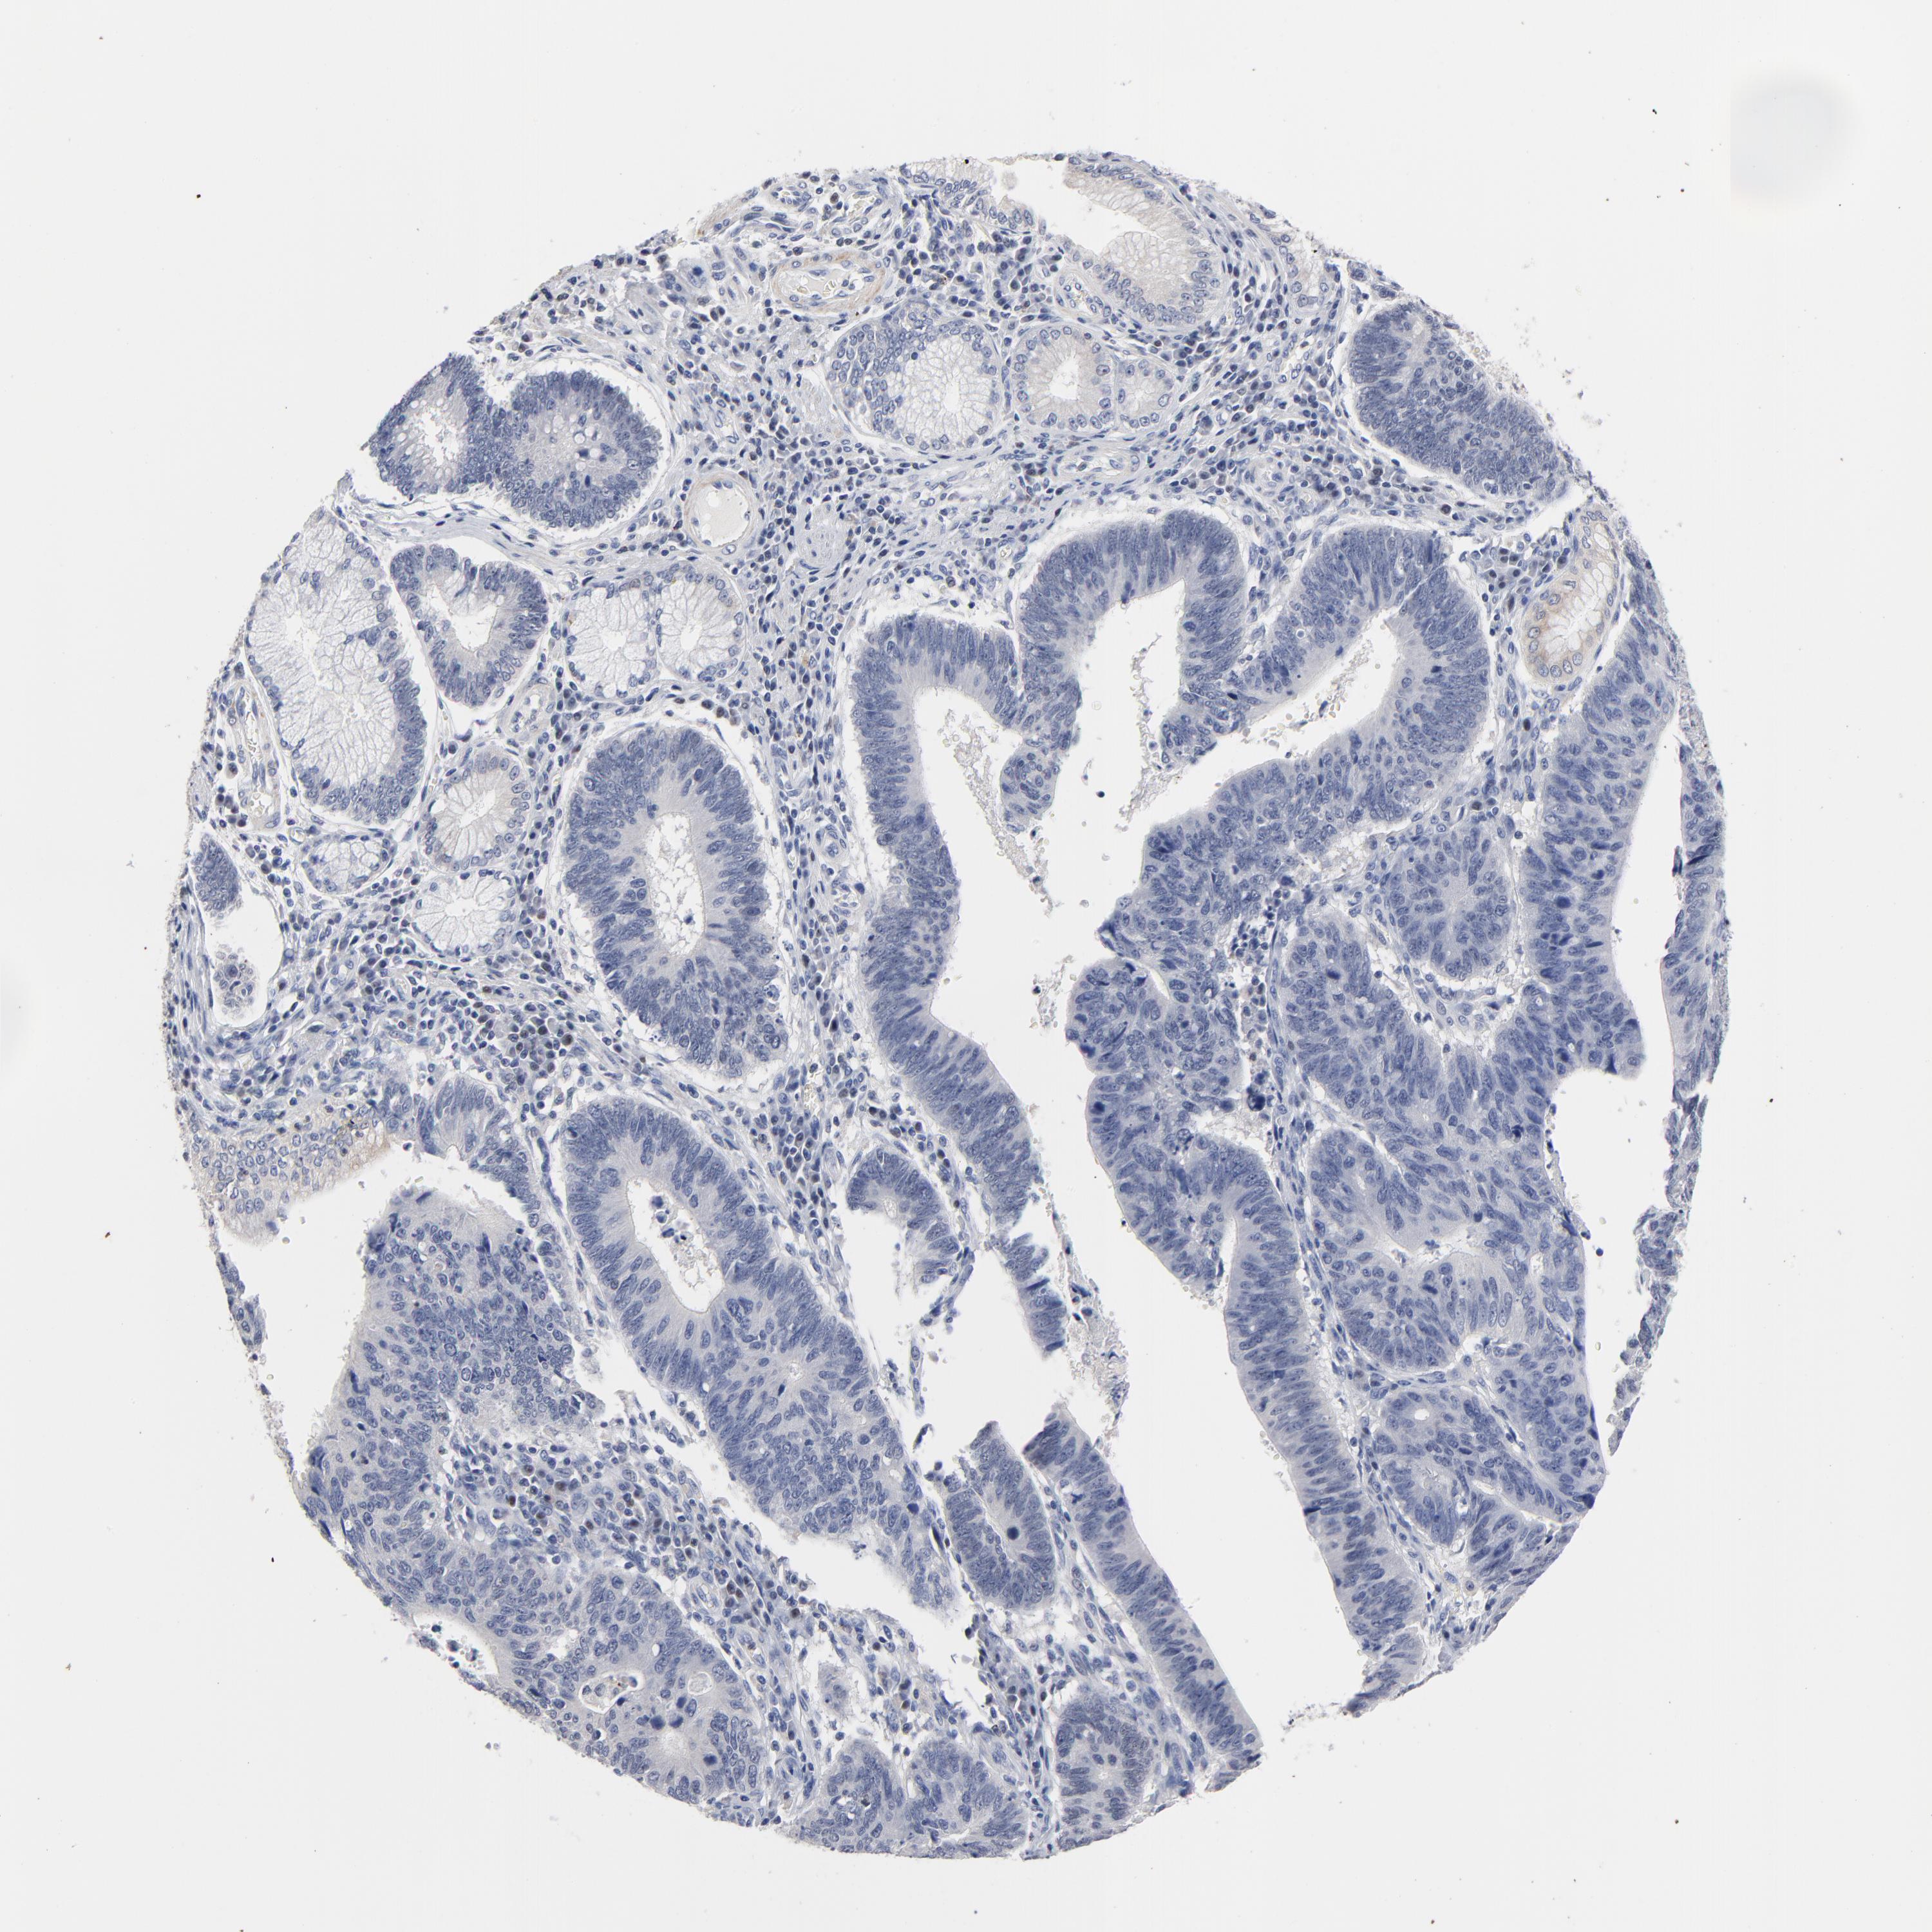

STOMACH CANCER - Protein expressioni

A mouse-over function shows sample information and annotation data. Click on an image to view it in a full screen mode. Samples can be filtered based on level of antibody staining by selecting one or several of the following categories: high, medium, low and not detected. The assay and annotation is described here.

Antibody stainingi

Antibody staining in the annotated cell types in the current human tissue is reported as not detected, low, medium, or high, based on conventional immunohistochemistry profiling in selected tissues. This score is based on the combination of the staining intensity and fraction of stained cells.

Each image is clickable and will lead to virtual microscopy that enables deeper exploration of all samples and also displays staining intensity scores, fraction scores and subcellular localization as well as patient and tissue information for each sample.

Antibody HPA002911

Staining

High

Medium

Low

Not detected

Intensity

Strong

Moderate

Weak

Negative

Quantity

>75%

75%-25%

<25%

None

Location

Nuclear

Cytoplasmic/membranous

Cytoplasmic/membranous,nuclear

Adenocarcinoma, NOS